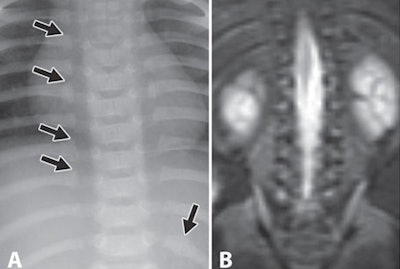

| A 3-month-old abused boy was brought to the emergency department with facial bruises and multiple fractures. Initial anteroposterior radiograph (A) of the chest shows multiple posterior rib fractures (arrows). Coronal MRI short-tau inversion recovery (STIR) image (B) of the chest shows no signal abnormality in posterior ribs or chest wall. Images courtesy of the American Journal of Roentgenology. |

Whole-body MRI had low sensitivity of 57% in identifying signal abnormality in areas of rib fractures seen with radiography.

"Although whole-body MRI performed somewhat better for the detection of rib fractures, with moderate agreement with the skeletal survey reference standard, sensitivity of 57% is discouraging," the authors noted. "This limitation is further compounded by the inability of whole-body MRI to localize injuries to specific ribs."